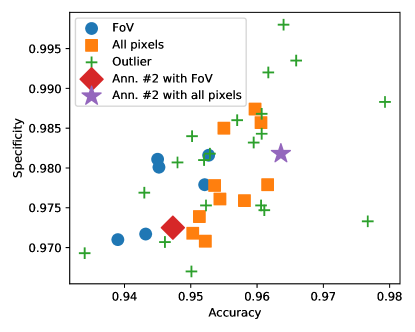

The results are summarized in Table 2 and plotted in Figure 3 in the accuracy-specificity plane. Surprisingly, 20 out of the 36 papers with image level scores turned out to be outliers. The ranking in Table 2 shows that almost all papers where the use of all pixels was accepted outperform those evaluating under the FoV mask, clearly showing the expected skew in the evaluations. A similar pattern can be seen in Figure 3: the scores where the use of the FoV mask was accepted tend to have lower accuracy and specificity scores than those where the use of all pixels was confirmed.

In some papers (such as (Wu et al., 2020)), multiple triplets of aggregated scores are reported to illustrate the effects of the various steps of the proposed methods. Similarly to the image level analysis, the majority rule is applied to make clear decisions about the region of evaluation used by the authors. The results are summarized in Table 3 and plotted in Figure 5. Again, we assigned 3 labels to the papers, in 30 cases the use of the FoV was accepted, in 18 cases the use of all pixels was accepted, and 16 papers were classified as outliers (the scores do not pass the test with either of the hypothesised regions). As before, the ranking in Table 3 and the illustration in Figure 5 confirm the expected bias in the evaluations: the algorithms evaluated on all pixels tend to have higher accuracy and specificity scores, in general.

In Figure 6 we have plotted the distribution of algorithms and evaluation methodologies in the adjusted accuracy-specificity plane. The plot shows that after eliminating the bias, the algorithms evaluated with all pixels have lower accuracy and specificity scores than those evaluated with the FoV mask. The independent two-sample t-test shows that the difference is statistically significant with a p-value of . The reason for this surprising phenomenon is that using all pixels to evaluate less effective techniques results in performance scores comparable to or even higher than those of more effective techniques evaluated under the FoV mask, and this brings publicity to less effective approaches.

Finally, we compare the performances of the methods by their operating principles. We have introduced 4 categories: deep learning, classical (thresholding, filtering, morphology, region growing), supervised (feature extraction and supervised machine learning, but not deep learning), and others (dominantly graph-cut based segmentation techniques). The results presented in Figure 6 show that deep learning techniques increase the accuracy by almost 1% compared to the best performing classical and supervised techniques.